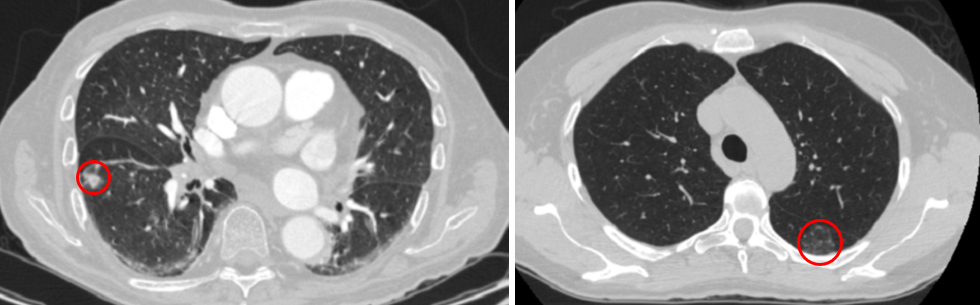

Refer to caption

Figure 4: Example of nodules assigned to experts based on their volume and diameter. The nodule on the left, which has a lower probability of belonging to the first expert, is smaller in terms of volume and diameter compared to the nodule on the right.

Experiment 3: Finally, we conduct an experiment to gain an insight on how the data instances are split between the two experts. The LIDC-IDRI dataset is accompanied by a few nodule-related properties, determined by the radiologists. These features include volume, diameter, x𝑥x center of mass and y𝑦y center of mass. We calculated the correlation between the output of the gating network and these features. While the correlations with volume and diameter are 0.580.580.58 and 0.770.770.77, respectively, we observed no correlation with the centers of mass. It should be noted that the inputs to the proposed MIXCAPS are cropped nodule regions. In other words, the model has no access to the location of the nodule. Therefore, the almost zero correlations with the centers of the mass is completely expected. The observed correlations between the gate outputs and the volume and diameter imply that larger nodules have higher probabilities of being assigned to the first expert. Fig. 4 shows two nodules in the test set. The left nodule, which has a volume of 496.32496.32496.32 and diameter of 9.8239.8239.823, has a low probability of belonging to the first expert, whereas the nodule on the right, with a volume of 6663.446663.446663.44 and diameter of 23.34723.34723.347, has a high probability of being assigned to the first expert. In other words, the first expert tends to handle larger nodules, compared to the second expert.